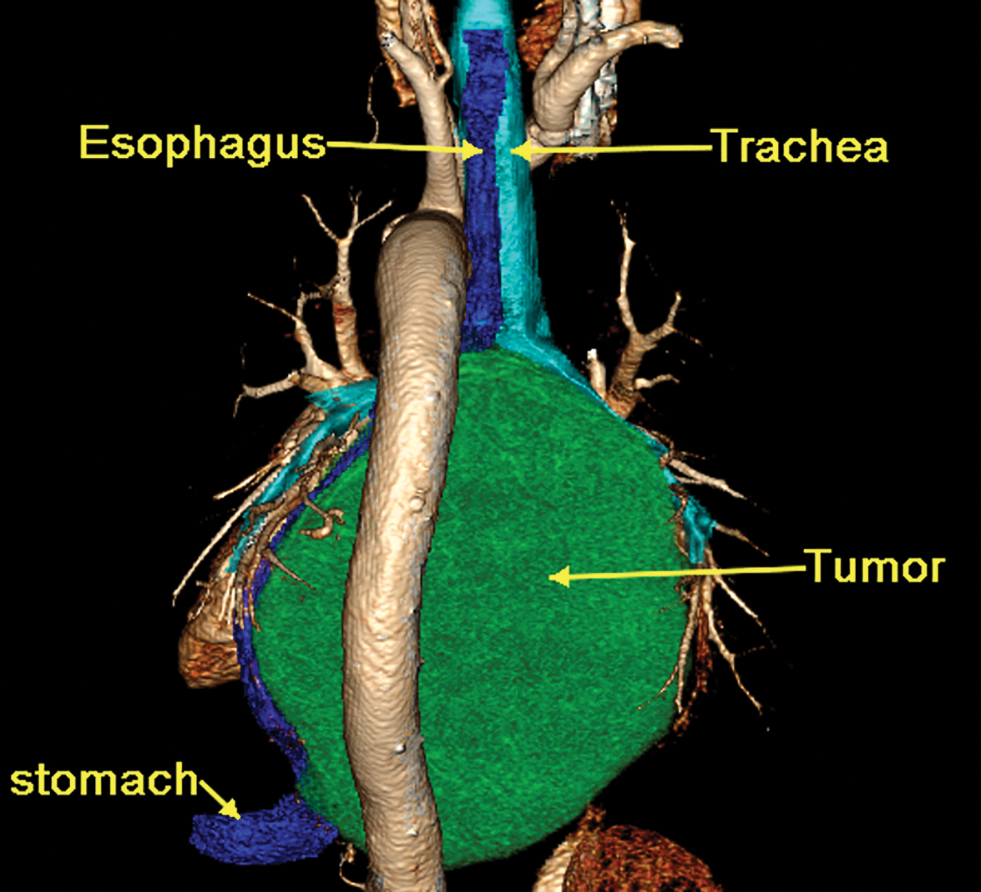

A 65-year-old man was referred to our hospital for investigation of atypical chest tightness of gradual onset over the previous 6 months. He denied weight loss, dysphagia, upper GI bleeding, reflux, or other symptoms. Blood and urine biochemistry showed almost normal results. However, transthoracic echocardiography revealed a solid echoic mass of approximately 16 cm behind the left atrium and significant compression of the left atrium. Chest computed tomography (CT) with contrast administration was performed. The examination was also completed by volume rendering reconstruction (VR) (Fig. 1) and revealed a solid mass of approximately 163 × 73 mm (the volume was 1308.92 mm3) visible behind the left atrium. The heart was compressed forward, the adjacent left atrium was significantly compressed, and the adjacent bronchi and esophagus were significantly compressed and displaced. A barium swallow study revealed that the lower esophagus was clearly shifted to the left under pressure, partially shifted forward in the left anterior oblique position, and shifted backward in the right anterior oblique position (Fig. 2). The barium meal passed smoothly. Considering that the patient had severe cardiac symptoms, thoracotomy was performed emergently. During the operation, the tumor was found to be approximately 17 cm in diameter and located in the posterior mediastinum, with unclear boundaries in some areas, abundant blood vessels on the surface, and cystic firmness in texture. The tumor was punctured with a thick needle to extract the internal fluid, which was bloody and mixed with sediment. After suction, the cyst wall was sutured and used for traction. The tumor wall was free along the edge of the tumor, with obvious oozing but no obvious blood-supplying artery. Because the source of the tumor was not known before the operation, the operation was very difficult. Further exploration on a subbase revealed that the tumor originated in the esophagus and had a short, wide pedicle on the lateral wall of the esophagus. Although the origin of the tumor has been clarified thus far, it is still difficult to completely remove the tumor. Fortunately, the entire tumor was finally removed with difficulty from meticulous operation. Postoperative pathological examination showed that the tumor was grayish yellow in section, had cystic firmness, was soft in quality and yellowish and sticky and frozen in appearance; part of the gray matter was broken, and part of the envelope was yellowish dark red. The diagnosis was an esophageal gastrointestinal stromal tumor with nuclear division <5/50 HPF (Fig. 3). The tumor basal margins were negative, and lymph node examination showed no cancer metastasis. Immunohistochemical indicators were as follows: SMA (−), S-100 (−), actin (+), desmin (−), PCK (−), EMA (−), VIM (+), CD34 (+), c-kit (+), Dog-1 (+), MDM-2 (+), CDK4 (−), and KI67 (+4%). After a multidisciplinary meeting, the patient received adjuvant therapy. Through multidisciplinary consultation, the patient received oral treatment with 400 mg of imatinib once daily after the operation and was closely followed up with chest CT scans (Fig. 4) or the barium esophagram every 6 months. After 3 years, the patient showed no sign of local recurrence with regular barium esophagram (Fig. 5), and no abnormally enlarged lymph nodes shadows were found on CT scans of the chest and abdomen performed during the follow-up.

Figure 1: Three-dimensional reconstruction of a 16-slice contrast computed tomographic scan revealed that a solid mass (CT values of 30 HU in the scan phase and 82 HU in the arterial phase) of approximately 163 × 73 mm was visible behind the left atrium, the heart was clearly displaced, and the main bronchus was obviously compressed